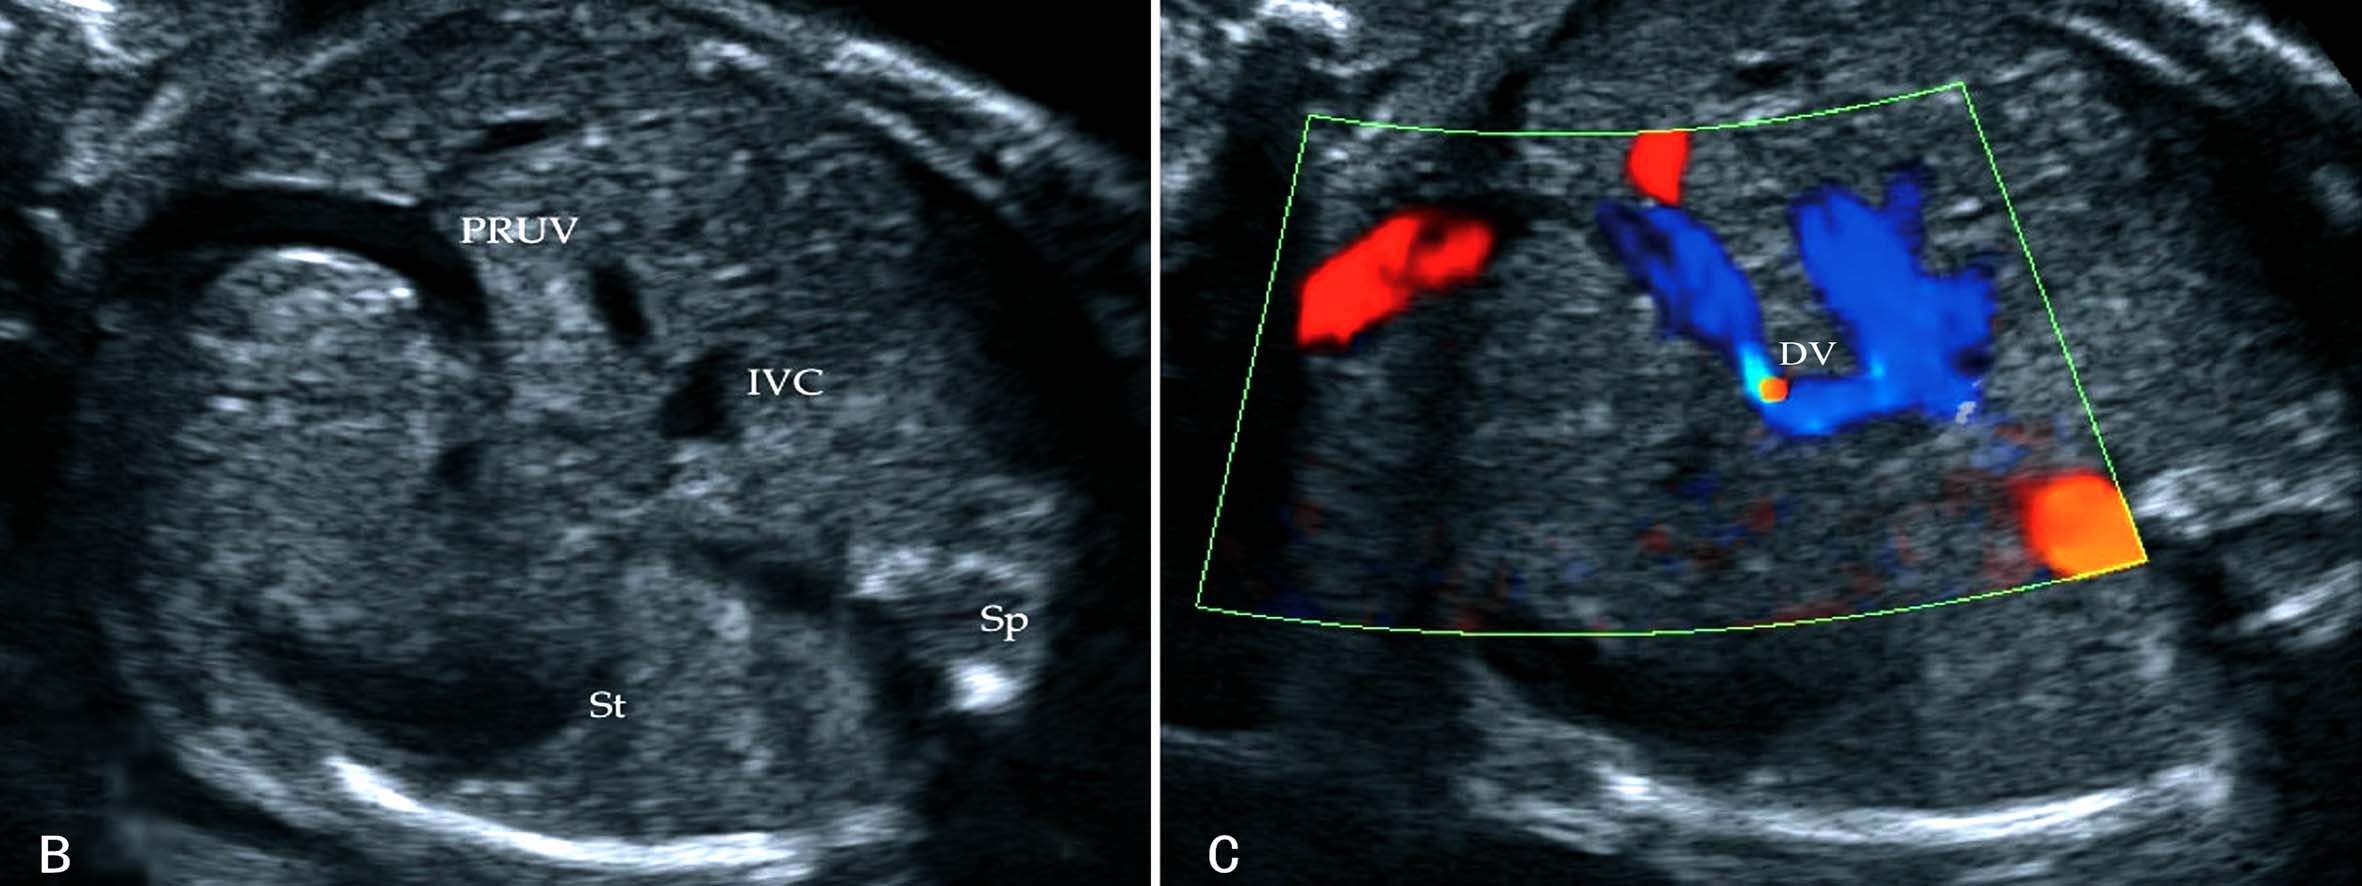

胚胎4周末右脐静脉开始闭锁,第7周时消失,形成正常的左脐静脉循环(图7A)。如右脐静脉不闭锁退化而左脐静脉闭锁,右脐静脉经过肝脏与静脉导管相连进入静脉导管,或绕过肝脏直接与下腔静脉或右心房相连(图7B),形成持续性右脐静脉7。在Hill等1994年进行的回顾性分析中,在15237例产科超声检查中发现了33例PRUV,产前超声检查显示率为0.21%(1:476);其中有18.2%(6/33)的伴有严重的先天性发育异常;在另一篇研究报道中,研究者在低风险胎儿中发现PRUV为1:526,其中17例胎儿合并其他部位的畸形,包括无脑儿、复杂性心脏畸形、双侧唇裂、孤立肾、单脐动脉等。

胎儿腹部横切面显示胃泡和脐静脉以后观察胆囊的位置可以确定脐静脉走行。正常脐静脉穿过脐轮后走行于胆囊的左侧,在胆囊与胃腔之间可以显示脐静脉的回声(图8A);如果在胆囊右侧显示脐静脉回声即可明确右脐静脉的诊断((图8B));肝内型持续性右脐静脉进入肝脏后PRUV需要转向左侧与静脉导管连接(图9)。连续追踪扫查如果显示脐静脉周围或一侧无肝脏实质,则提示为肝外型持续性右脐静脉。一般认为,后者常合并其他部位的发育异常,并可以合并染色体异常。

图11-54 持续性右脐静脉声像图